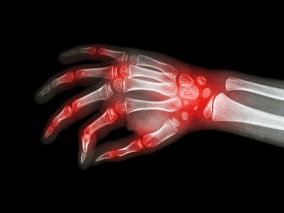

1小时条评论39岁女性,2年前诊断为系统性红斑狼疮、胃食管反流,近几周关节肿胀、手肩肘膝盖僵硬,症状晨重,活动后减轻,无痛感,四肢无力加重。实验室检验结果显示多种酶浓度增高,说明肌肉细胞坏死。其最可能的诊断是什么? 1﹒临床病史 患者:女性,39岁。症状:关节肿...

1小时条评论32岁女性,双手小关节肿痛2年,体检发现白细胞减少1个月,抗SSa抗体+。如何鉴别以关节炎为主要病变的疾病? 患者女性,32岁,因双手小关节肿痛2年,体检发现白细胞减少1个月来门诊就诊,初步病史采集如下: 患者于2年前无明显诱因下出现双手小关节肿痛,以近端指间...